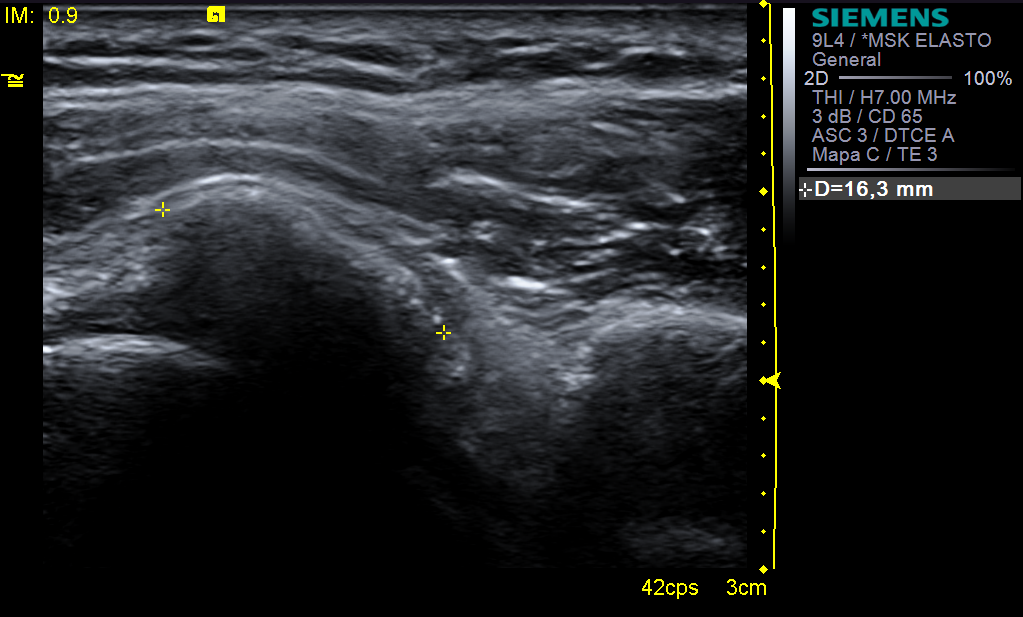

En las ecografías vemos:

Informe radiológico: se visualiza calcificación dura con sombra acústica posterior en espesor del tercio anterior-medio del tendón del supraespinoso, que mide 2cm APxL.